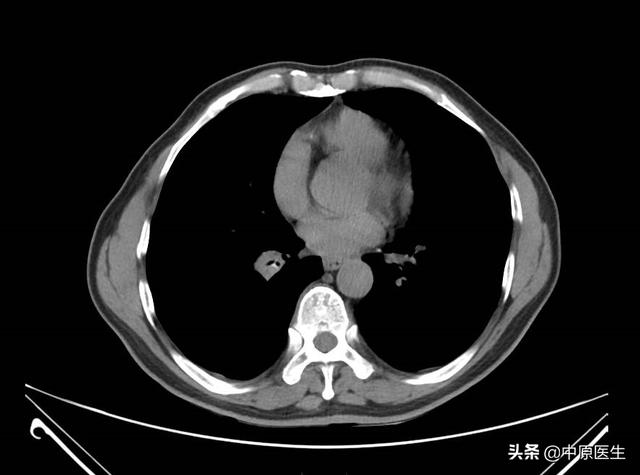

纵隔脂肪间隙模糊, 前中上纵隔偏左见不规则软组织影,大小约10.